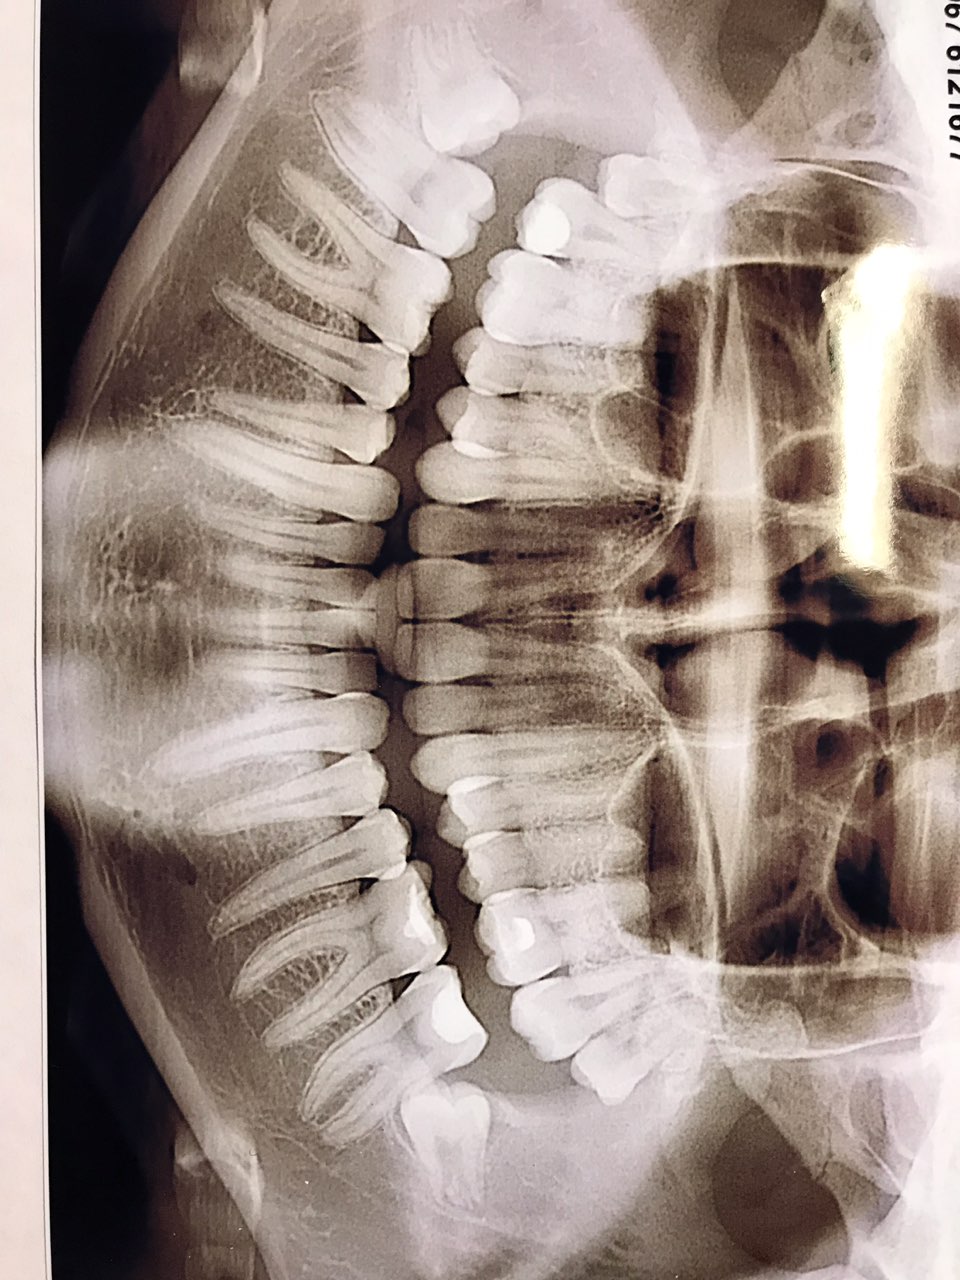

Power_andrey Опубликовано 21 декабря, 2018 Опубликовано 21 декабря, 2018 Дочка была на приёме у стоматолога, жалобы на периодические боли, стоматолог сказал надо удалять зубы мудрости, они растут и давят на зубы. Записалась на консультацию к хирургу, в частную клинику, сделала понорамный снимок. Сегодня хирург осмотрел и сказал, что удалять нет необходимости. Теперь не знаем что делать, кто разбирается в данном вопросе подскажите пожалуйста, что же всё таки делать.

kotyuk Опубликовано 23 декабря, 2018 Опубликовано 23 декабря, 2018 Дочка была на приёме у стоматолога, жалобы на периодические боли, стоматолог сказал надо удалять зубы мудрости, они растут и давят на зубы. Записалась на консультацию к хирургу, в частную клинику, сделала понорамный снимок. Сегодня хирург осмотрел и сказал, что удалять нет необходимости. Теперь не знаем что делать, кто разбирается в данном вопросе подскажите пожалуйста, что же всё таки делать. А болит именно в области зубов мудрости (восьмерок)? Они не ровно заложены, что встречается довольно часто. Это может искривить зубной ряд (я травматолог, а не стоматолог, но у меня жена ортодонт + у меня именно так и произошло, из-за чего пришлось удалять). Но происходит это не всегда. На счет боли не знаю. На мой взгляд относительные показания к удалению нижних восьмерок есть. Но относительные на то и относительные, что нужно смотреть, в них ли причина.